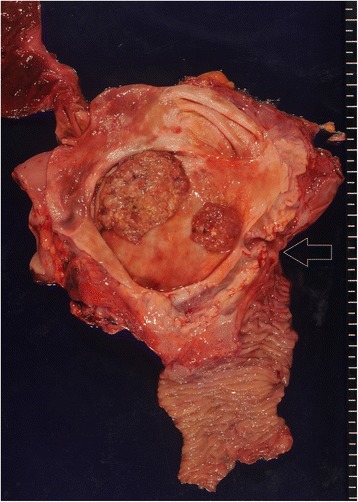

The resected specimen demonstrated tumors in the inferior and middle bile ducts (Fig. 5). Immunostaining was positive for CDX2 and negative for MUC1, MUC2, MUC5AC, MUC6, and p53. According to the Union for International Cancer Control (UICC), sixth edition rules, this case was stage 0 (Tis, N0, and M0). A postoperative histopathologic examination revealed a well-differentiated tubular adenocarcinoma, which entirely remained within the mucosal layer, and no lymph node metastasis was found (Fig. 6). The postoperative course was uneventful, and the patient was discharged 10 days after surgery and has remained disease-free for 21 months.